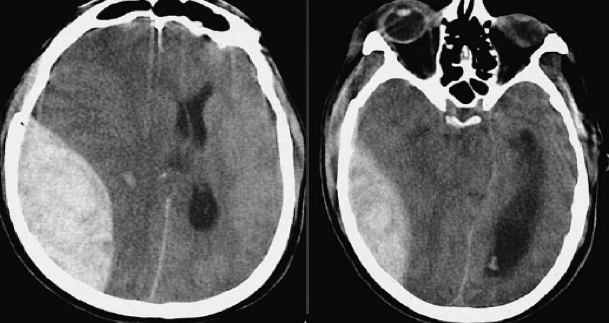

LESIONES SECUNDARIAS

Son debidas al aumento de la presión intracraneal o a las herniaciones, la importancia de su diagnóstico radica en que son lesiones prevenibles y tratables. Son:

1- Edema cerebral difuso: Aparece en las primeras 48 horas del traumatismo. Se identifica por:

- Produce efecto de masa.

- Borramiento de surcos = pérdida de la interfase sustancia gris-sustancia blanca.

- Otros: signo del cerebelo blanco, falsa hemorragia subaracnoidea…

2- Herniaciones encefálicas

Transtentorial: puede ser unilateral/uncal o bilateral/central.

- Por descenso del contenido supratentorial a través de la tienda del cerebelo.

- Puede ser unilateral o Uncal = descenso del uncus hacia el interior de la cisterna supraselar.

- Dilatación del asta lateral contraletaral

- Dilatación de la cisterna ambiens y prepontina ipsilateral.

- Bilateral o Central = obliteración las cisternas basales

- Hay riesgo de infartos por compresión la ACP y perforantes.

- Pueden producir hemorragias de Duret (mesencéfalo) o de Kreonhan (pedúnculo cerebral contralateral)